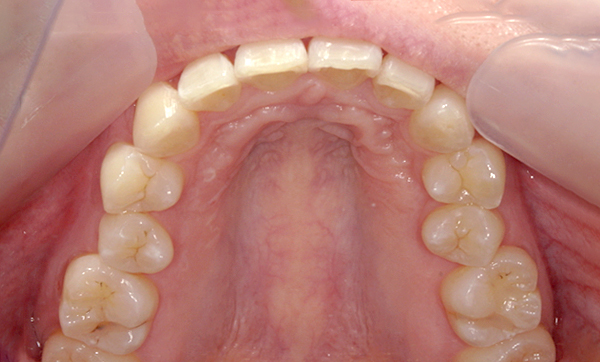

症例:上下顎の部分矯正

症例_007 「出っ歯」症例

治療期間:9ヶ月金額:54万円+税60代女性出っ歯捻転歯